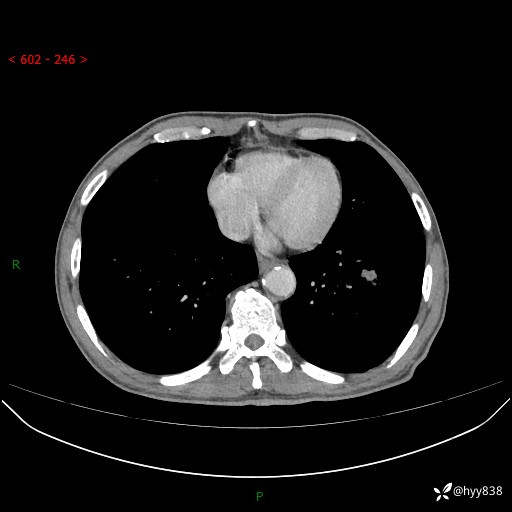

辅助检查:CT

胸部CT平扫

增强动脉期+静脉期

各期CT值:38Hu 52hu 55hu